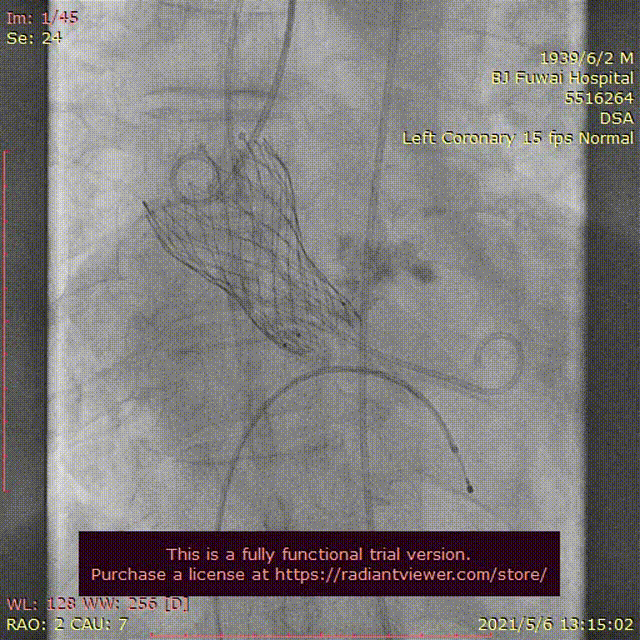

手术当天,病房护士提前行左肘正中静脉留置针作为补充液体通路;患者送达介入导管室后,省去经颈内静脉穿刺行中心静脉置管、经食道超声检查、术前导尿和麻醉师全身麻醉及气管插管或喉罩通气等过程;患者经过消毒及铺单后。半支(50mg)利多卡因局部麻醉后,穿刺右桡动脉作为辅入路,立即检测动脉血压;四支(400mg)利多卡因局部麻醉后,血管超声引导精准穿刺右股总动脉,两把ProGlide预埋处理后,作为主入路,置入20F 长导引鞘管(戈尔公司),立即动脉给予肝素5000单位;经右股静脉入路,将漂浮电极送入右心室心尖,临时起搏器调整至120次/分调试及测试患者的耐受性。主入路和静脉起搏器入路建立过程中,密切关注患者的血压心率等生命体征无明显异常,患者无明显不适。经右桡动脉送角度猪尾于右冠窦,采用右窦中心投照体位(右2°,足8°)行主动脉根部造影;

交换为头端塑形好的Landerquist超硬导丝,采用23 mm NUMED-II球囊对狭窄钙化的主动脉瓣进行预扩张,同时造影显示球囊完全封闭主动脉瓣,几乎无反流;

根据瓣上结构测量及球囊预扩张效果,采取“Down-size”策略,选择A-26 Venus A瓣膜,通过输送系统完成过弓和跨瓣;Venus A瓣膜精准定位于瓣环水平,

在临时起搏器控制心室快速起搏下完成瓣膜释放;

由于本例患者原瓣叶融合钙化较重,采用“瓣中瓣”技术植入另外一个A-26 Venus A瓣膜,

采用23mm NUMED-II球囊对植入的瓣膜进行后扩张;

最后造影显示新植入的瓣膜位置理想,少量瓣周反流,

跨瓣压差由术前30 mmHg下降至4 mmHg;即刻经胸超声评估主动脉瓣位植入生物瓣峰值流速为2.0 m/s,平均跨瓣压差为16 mmHg,少中量瓣周反流,左室射血分数为45%;评估患者心率为67次/分并且心电图较术前无明显异常,故即刻拔出临时起搏导线。整个手术过程仅采用局部麻醉,无任何镇静剂使用,患者全程清醒,配合良好,在球囊扩张主动脉瓣及瓣膜释放过程的血压及心率等生命体征与既往全麻相比无明显异常,患者略感心慌及无力。(图3)。术后患者平卧24 小时即下床活动,进行康复训练;采用阿司匹林100 mg (QD)和氯吡格雷75 mg(QD)行双联抗血小板治疗,术后4天顺利出院。

图3患者经导管主动脉瓣置换术及围术期操作

A:主动脉根部造影;B:23 mm球囊预扩张;C:26型号VenusA瓣膜植入;D:26型号VenusA“瓣中瓣”位置良好,少量瓣周漏;E和F:术前及术后经导管跨瓣压差;G:肘正中静脉留置针;H:患者全程清醒状态。